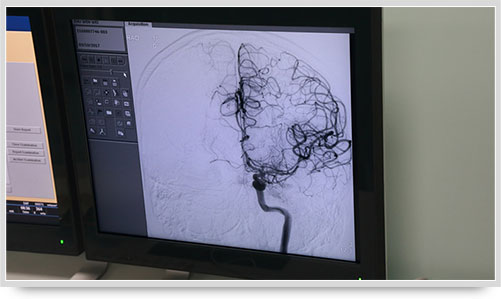

全脑血管造影术(DSA)是运用数字减影技术下进行的全脑血管摄片,因此又称数字减影血管造影。技术上一般采用局部麻醉,右侧股动脉穿刺、置管,再将一根造影管通过腹主动脉、主动脉弓,选择性进入左右颈内动脉和椎动脉后,分别造影,发现病灶后还应行三维血管造影。造影图像较以往所用的常规脑血管造影所显示的图像,更清晰和直观,一些精细的血管结构亦能显示出来,是目前国际上公认的血管性疾病诊断的“金标准”。

弓上造影、超选到颈内动脉、椎动脉......在数字减影技术下,注入显影剂后,导管经患者右侧股动脉在体内推进,由于股动脉离脑血管距离较远,中间“路程复杂”,对施术医生的要求非常之高。

同时,手术台前的液晶显示仪屏幕上清晰地现显出导管的路径,在李主任的操作下准确到达指定检查部位,各条血管的“庐山真面目”清晰可见。